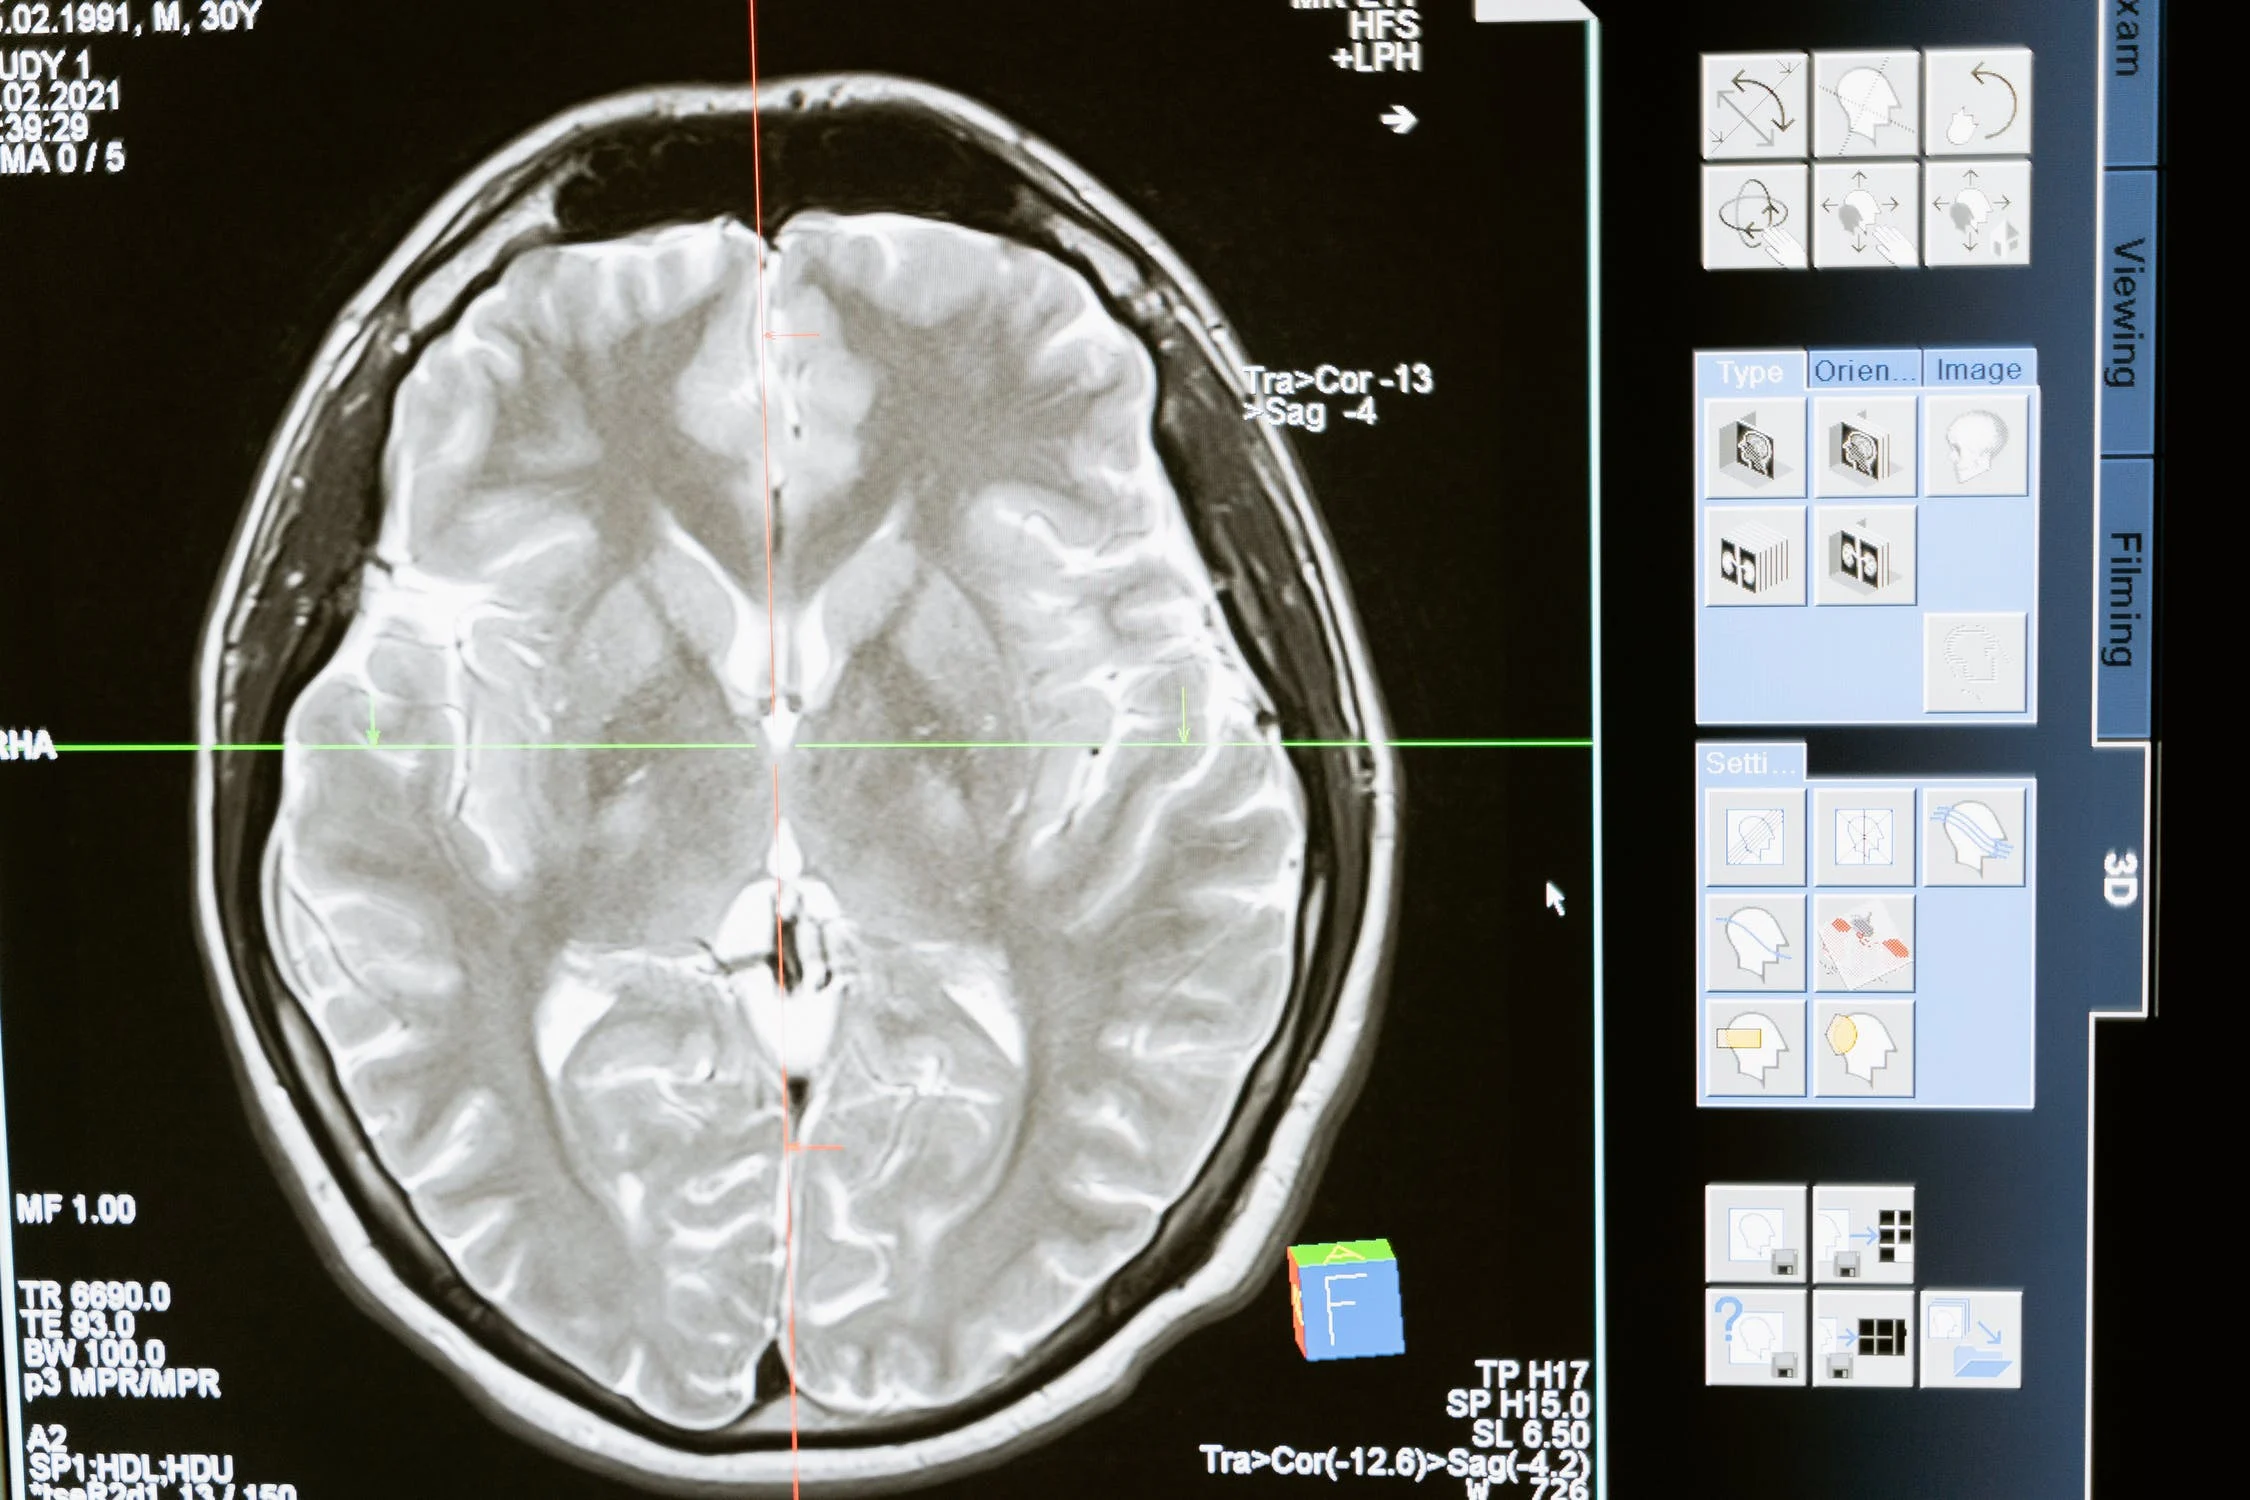

Las actividades propiasmente humanas como la conciencia ¿se pueden explicar sólo estudiando la funcionalidad física del cerebro? Este problema es relevante en la conceptualización de la Inteligencia Artificial.